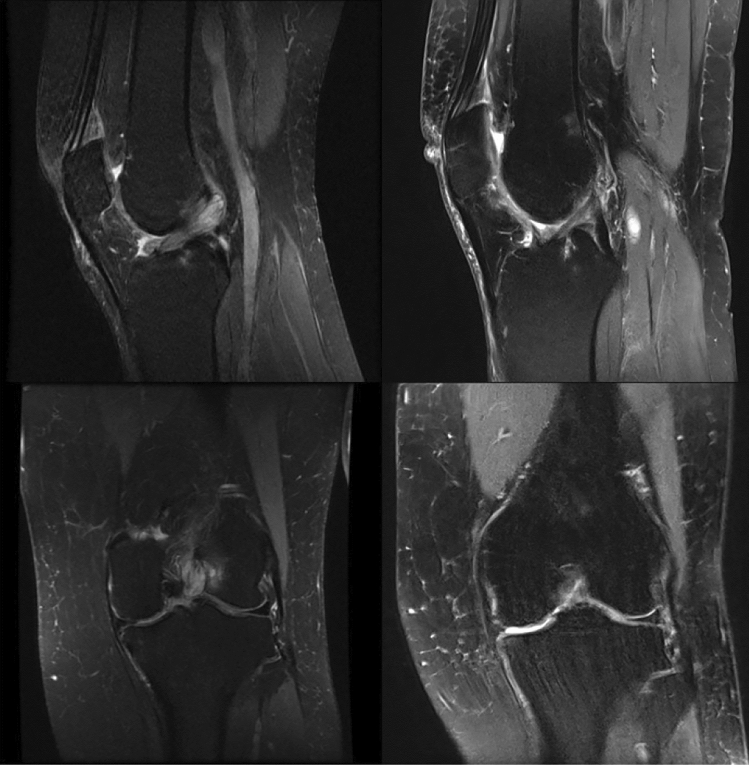

Preoperatively, all MRIs showed a hyperintense, bulky ACL, which occupied the intercondylar notch with an increased T2 signal and a mass-like configuration with “celery stalk” sign (Fig. 3). Continuity of the ACL could be observed in all MRI slices prior to surgery. Postoperatively, in Group I, also all patients’ MRIs showed continuity of the ACL (Fig. 3).

Fig. 3.

MRI of MDACL before and after treatment of partial resection

On initial MRI scans, mean thickness of ACL was 15.7 ± 2.4 mm (range 11–19 mm) in all patients. On average, ACLs in Group I were measured slightly thinner than in Group II (Group I: 14.6 ± 2.4 mm (range 11–19 mm) vs. Group II: 16.7 ± 1.9 mm (range 14–19 mm), p = 0.04).

Postoperatively, Group I showed a mean ACL thickness of 11.4 ± 3.6 mm (range 4–15 mm). Pairwise comparison of thickness values prior to and post-surgery in Group I did not show significant differences.

Mean ACL/intercondylar ratio was 0.61 ± 0.08 (range 0.50–0.71) in all patients. Subgroup analysis revealed a slightly greater ACL/intercondylar ratio in Group I than in Group II in preoperative MRI scans (Group I: 0.65 ± 0.06 (range 0.53–0.71) vs. Group II: 0.57 ± 0.08 (range 0.50–0.71); p = 0.02). After partial resection procedure, mean ACL/intercondylar ratio was 0.58 ± 0.22 (range 0.22–0.93) on follow-up MRI scans in Group I. Again, pairwise comparison of ACL/intercondylar values prior to and post-surgery in Group I did not show significant differences (Table 1).